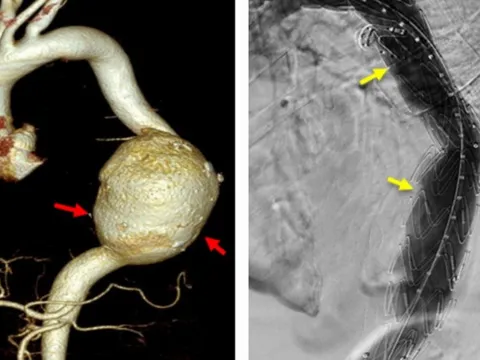

Cứu bệnh nhân nước ngoài bị vỡ túi phình động mạch chủ khổng lồ

TPO - Ngày 18/6, thông tin từ Bệnh viện Đa khoa S.I.S Cần Thơ cho biết, tại đây vừa can thiệp kịp thời cứu sống bệnh nhân người nước ngoài bị vỡ phình động mạch chủ ngực có kích thước khổng lồ.